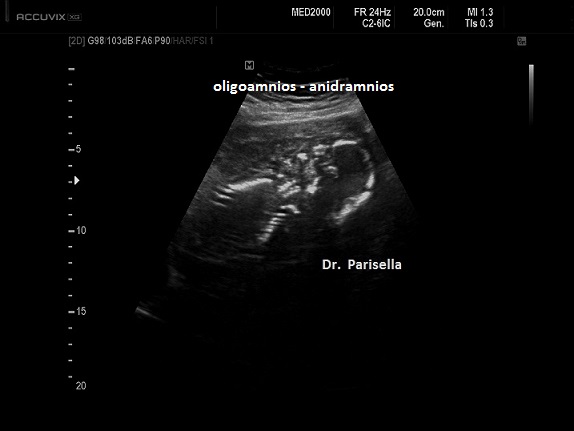

Possono essere presenti: idrope, cardioaptie congenite, labiopalatoschisi, oligoamnios, anomalie genito-urinarie, anomalie gastro-intestinali, anomalie del SNC.

La MICROMELIA SEVERA e l’ IPOPLASIA TORACICA SEVERA (legata al torace stretto con coste corte) sono i segni principali che indirizzano verso una corretta diagnosi. La POLIDATTILIA, sempre presente, è di tipo postassiale ed interessa sia mani che piedi. Spesso è presente idrope.

Sono presenti labiopalatoschisi, anomalie genitourinarie ed anomalie gastrointestinali. Può essere presente idrope ed ascite.